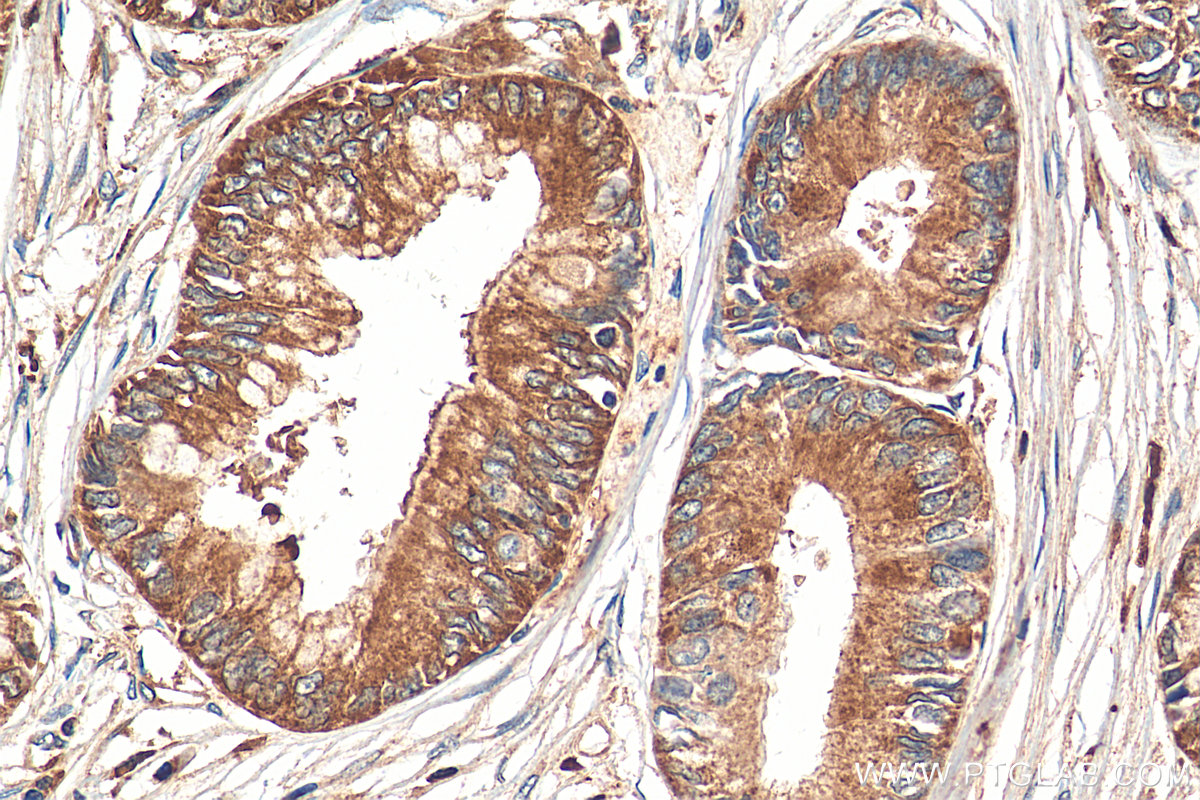

| Positive IHC detected in | human pancreas cancer tissue Note: suggested antigen retrieval with TE buffer pH 9.0; (*) Alternatively, antigen retrieval may be performed with citrate buffer pH 6.0 |

| Immunohistochemistry (IHC) | IHC : 1:50-1:500 |